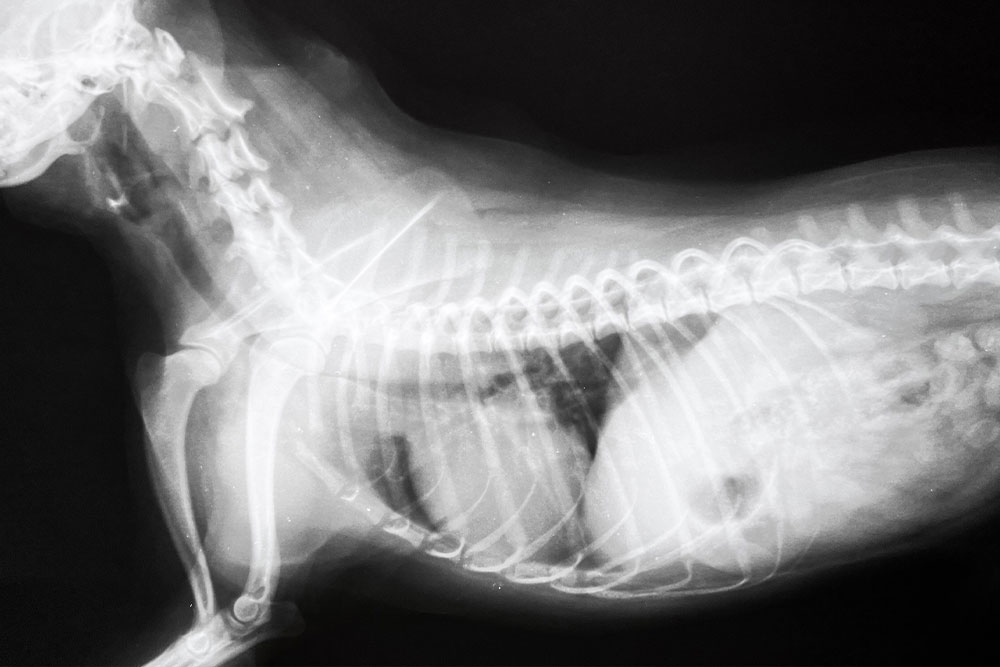

From there, imaging provides the objective picture:

- Radiographs (X-rays) taken during both inhalation and exhalation can reveal narrowing of the tracheal lumen (the hollow, tubular inner cavity of the windpipe) at different phases of the breathing cycle. A cervical collapse (in the neck) tends to be most visible on inspiration, while a thoracic collapse (in the chest) is more apparent on expiration.

For most pets, a physical exam and x-rays are enough to get a proper diagnosis. For cases that aren’t straightforward or for pet owners that want to pursue surgery to fix tracheal collapse, we may recommend:

Collapse is typically graded on a scale from Grade 1 (mild, about 25% reduction in tracheal lumen) to Grade 4 (near-complete collapse). That grade, along with the dog’s clinical symptoms, guides the treatment approach. Our team is experienced in respiratory assessment and will recommend the appropriate diagnostics for each patient’s presentation.